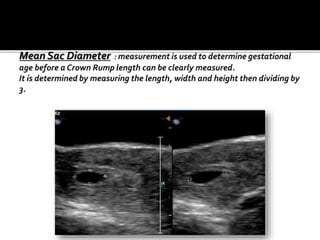

 MEAN SAC DIAMETER : the average internal

diameter of the gestational sac, is calculated

as the mean of theAP, transverse and the

longitudinal diameter.

Normally, a yolk sac will be present when MSD :

8 .0 mm.

Embryo will be present when MSD : 16.0 mm.

 MSD between 2-14 mm are accurate in

predicting the gestational age, before the

embryo is seen.